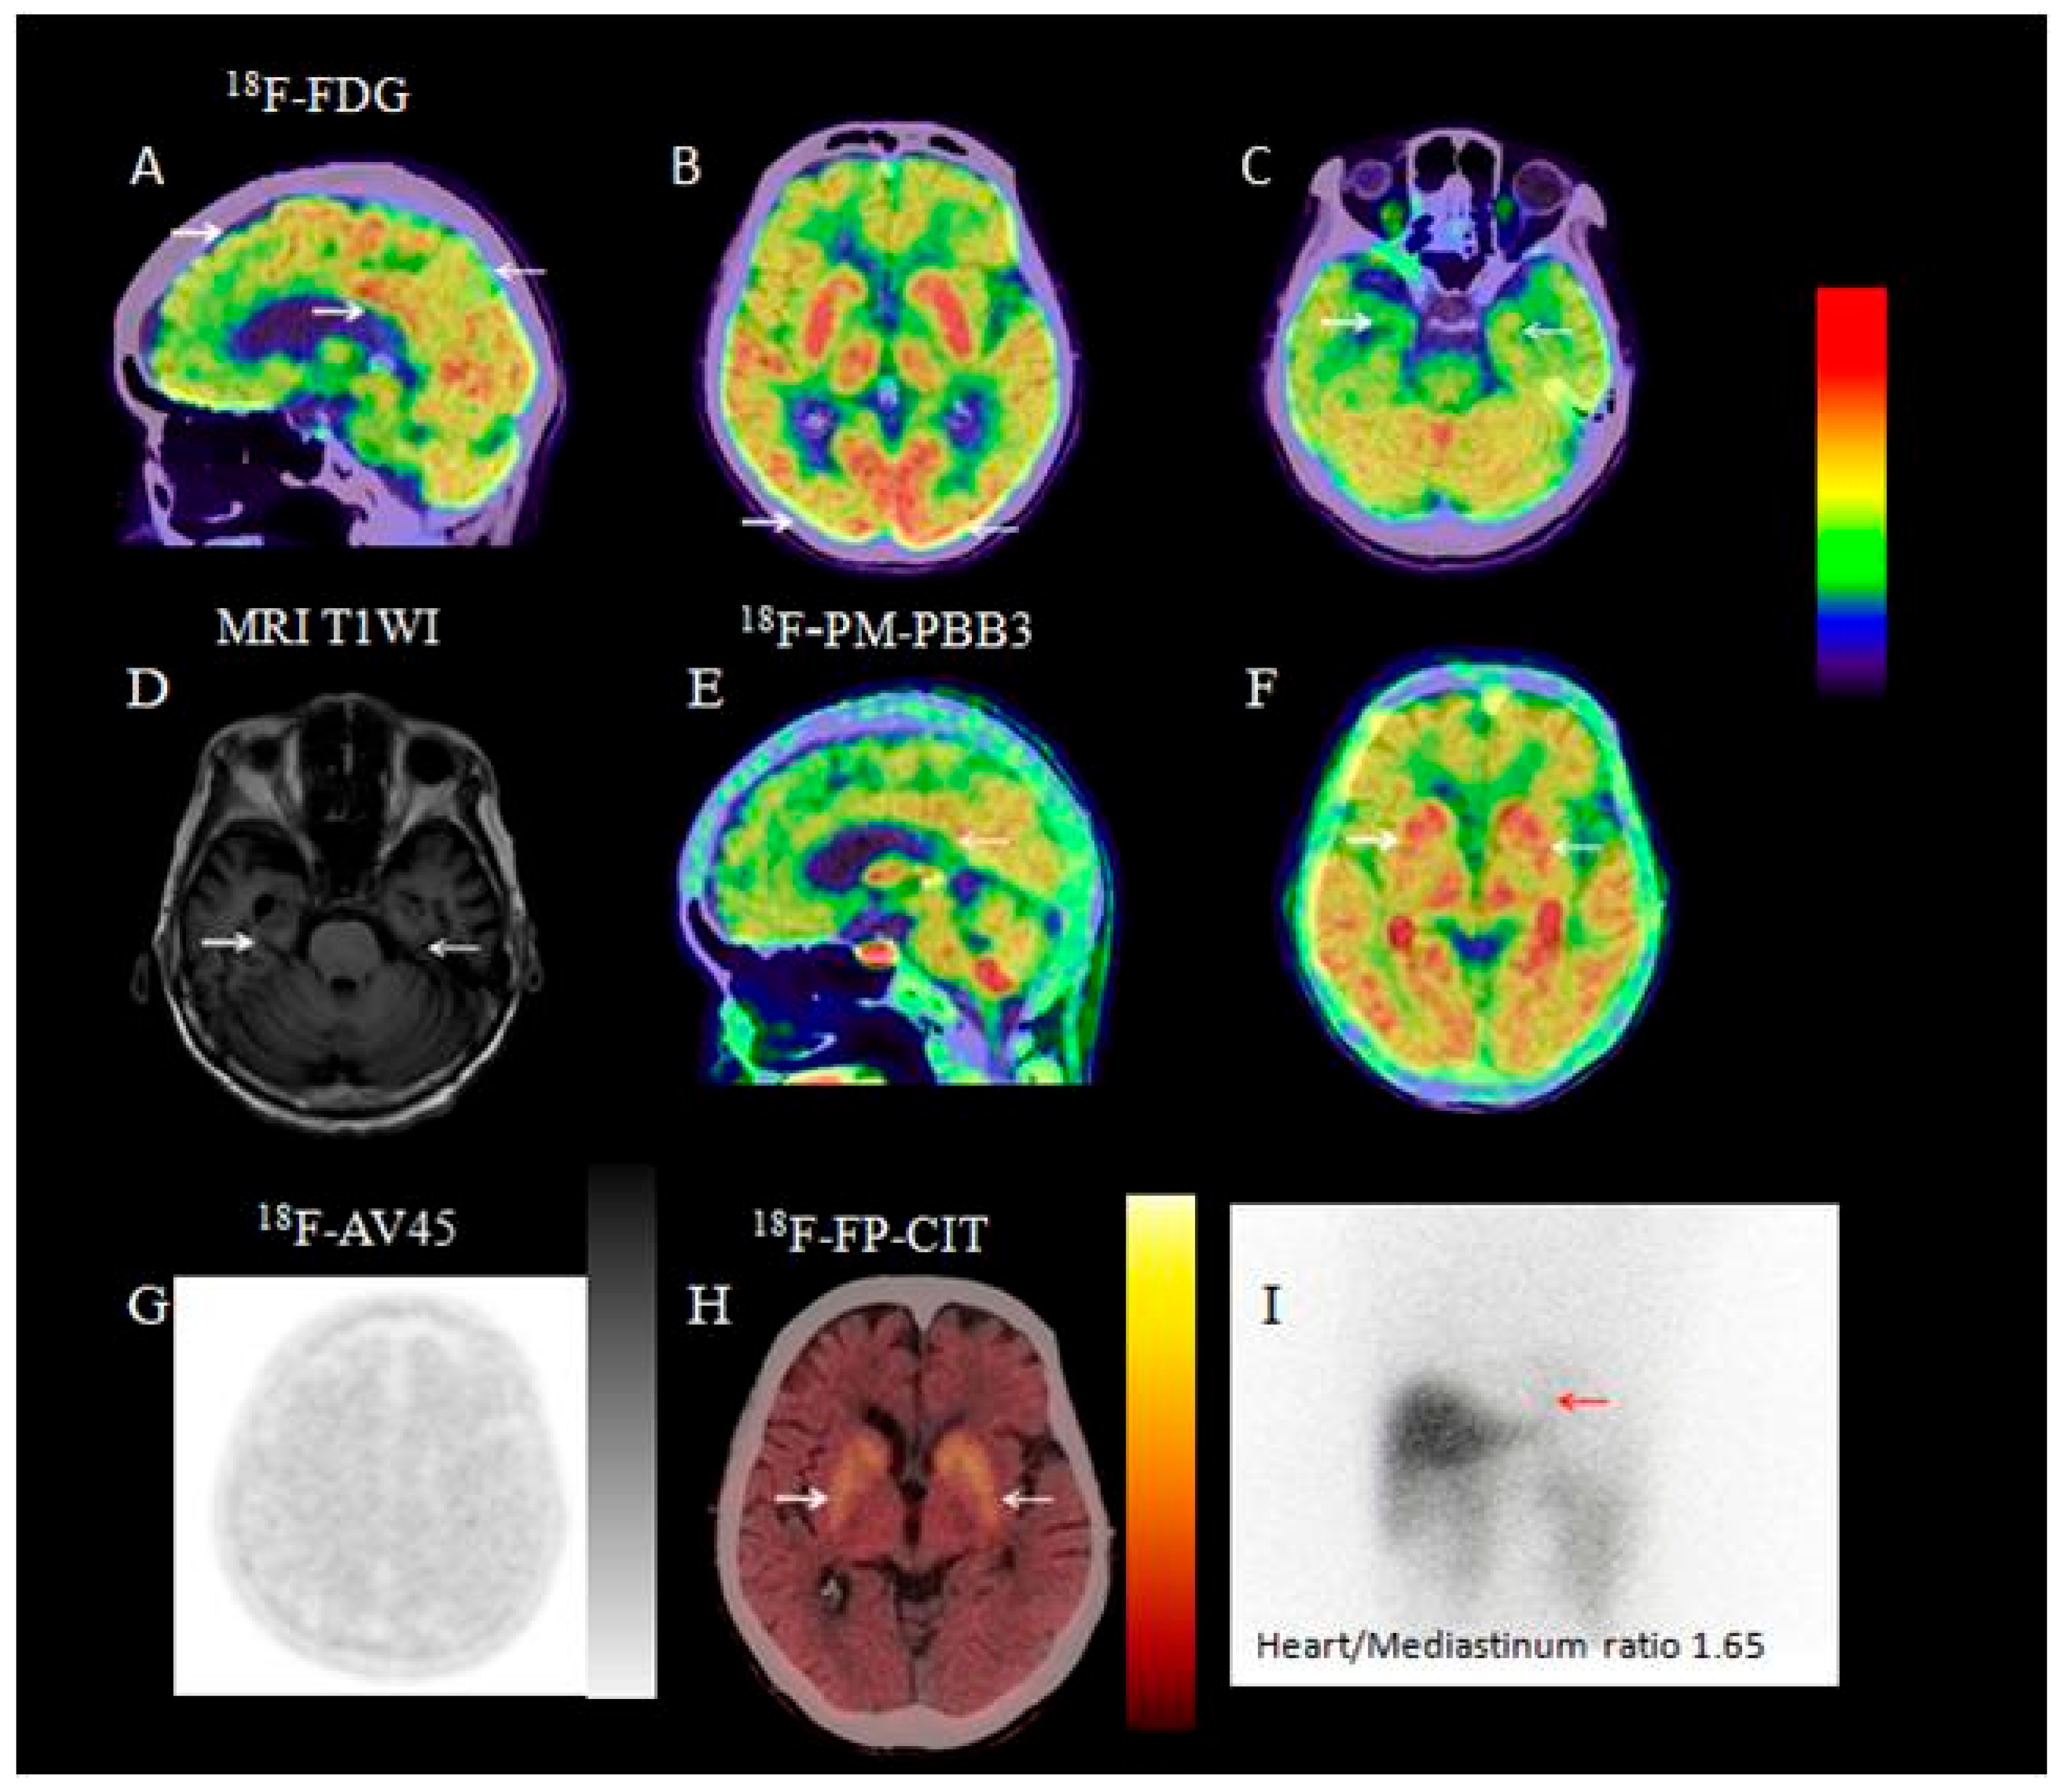

3.2.1. Visual Analysis of 18F-FDG PET/CT

3.2.7. Visual Analysis of 131I-MIBG SPECT

3.2.8. Visual Analysis of 18F-PM-PBB3 PET/CT